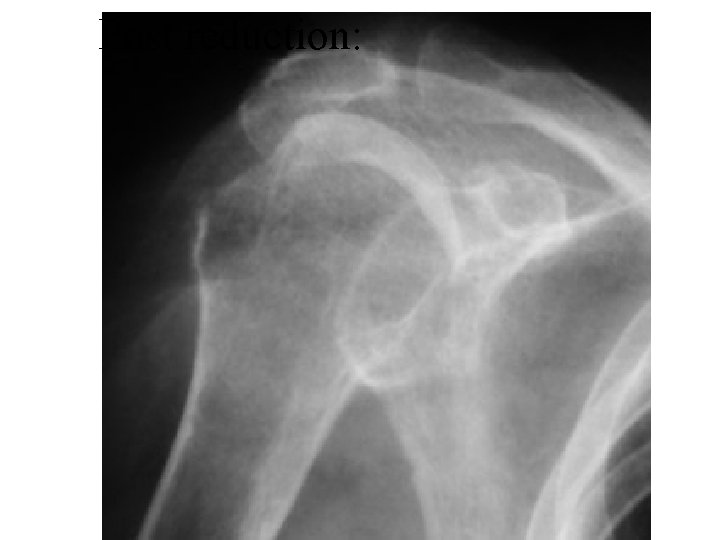

Luxatio Erecta:

Luxatio Erecta • 0. 5% • Usually axial load on abducted arm or indirect trauma • Presents with 100 -160 deg of abduction • Humeral shafts lies parallel to spine of scapula (infglenoid lies against chest wall) • Usually need ortho help • Wary buttonhole problem